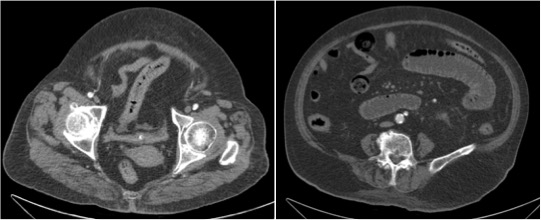

Paciente 89 años hospitalizada por dolor abdominal intenso y náuseas sin vómitos. El dolor es generalizado y no cede con tramadol.

Se realiza TC de abdomen en vacío y con contraste en fase portal:

Estamos ante un cuadro de isquemia intestinal en un paciente con bajo gasto cardiaco con afectación principal de asas intestino delgado, territorio vacularizado por la arteria mesentérica superior.

5º) Neumatosis intestinal y portal. Aire extraluminal.

Son signos poco frecuentes pero muy específicos de isquemia intestinal, E cercana al 100%. Se obsevan mejor en el TC SIN contraste.

La neumatosis intestinal consiste en aire localizado en la pared del intestino. Se produce por discontinuidad de la pared con paso de aire hacia las capas más externas y a las venas intramurales.

La presencia de neumatosis portal y mesentérica consiste en pequeñas burbujas de gas dentro de los vasos mesentéricos o que también pueden extenderse hacia las ramas intrahepáticas de la vena porta, encontrándose típicamente en la periferia del hígado.